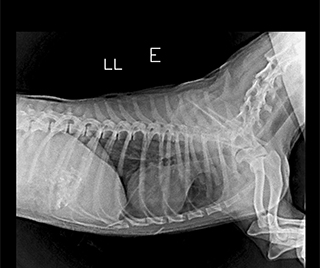

Radiologia Digital Direta / Digital Radiography

As radiografias geradas digitalmente podem ser transmitidas para iPad Apple®, notebooks e smartphones.

iPad com tela Retina Apple® possibilita a visualização das imagens com maior qualidade diagnóstica.

Envio Digital Automático (EDA) permite a distribuição das radiografias sem necessidade de impressão.

O responsável pelo paciente pode receber as radiografias em seu smartphone ou computador.

Radiologistas podem receber as imagens por e-mail para laudo, de forma prática. 100% DIGITAL